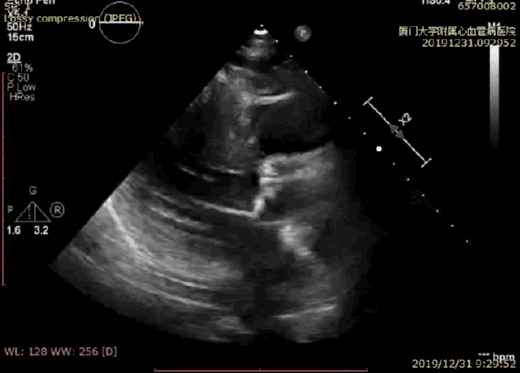

入院行床边超声提示:主动脉瓣重度狭窄伴轻度度关闭不全(Vmax: 4.4m/s,PGmax: 79mmHg,PGmean: 49mmHg,,AVA0.3cm2,EF: 59%);室间隔基底段增厚,左室下、后壁基底段运动幅度相对减低 ;二尖瓣后瓣环钙化伴中度反流;左室整体收缩功能正常。

术前超声显示瓣叶钙化,活动度明显受限

术后超声显示瓣膜位置良好

术后超声显示无瓣周漏

术后超声显示压差明显降低